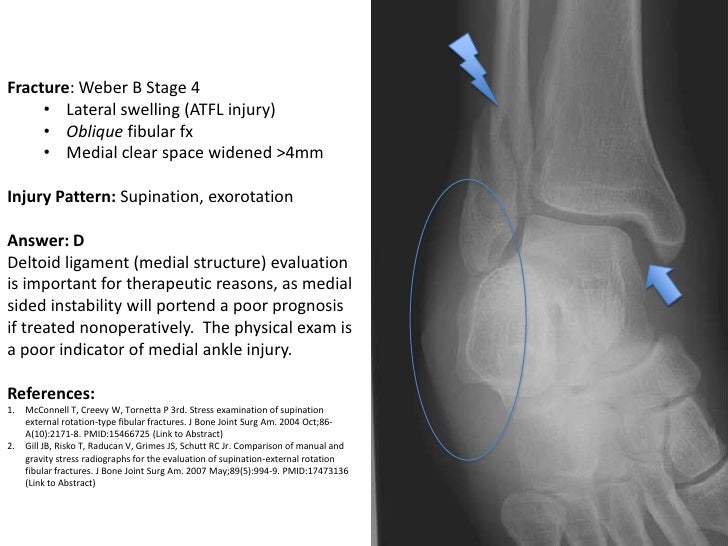

The syndesmosis is a long interosseous membrane that holds the fibula and tibia together and is composed of 4 ligaments at its most distal end. These ligaments restrict inversion and internal rotation forces. These secure the lateral aspect of the ankle by anchoring the fibula to the foot. The lateral collateral ligaments are composed of three ligaments: the anterior talofibular ligament (ATFL), calcaneofibular ligament (CFL), and posterior talofibular ligament (PTFL). The most common mechanism of injury that damages this ligament is foot eversion or an external rotation force due to the intense medial stresses these forces produce. When the deltoid ligament ruptures instead of the medial malleolus fracturing during a bimalleolar ankle fracture, it is known as a "bimalleolar equivalent" fracture. The deltoid ligament is the most common ligamentous injury during the medial malleolar fracture, causing joint instability. The deep portion is the strongest portion and extends from the medial malleolus to the talus. The superficial fibers extend from the medial malleolus to the navicular, sustentaculum tali of the calcaneus and the talus. These four ligaments are named the anterior tibiotalar ligament, posterior tibiotalar ligament, tibiocalcaneal ligament, and tibionavilcuar ligament, and they are divided into two portions: superficial and deep. The medial collateral ligament, or deltoid ligament, is a triangular-shaped ligamentous complex composed of 4 ligaments that stabilize the medial aspect of the ankle by anchoring the tibia to the foot. As stated above, the ankle is composed of the tibia, fibula, and talus articulating with each other, and these articulations are supported by strong ligamentous support on either side. The ankle joint is in the mortise and tenon joint classification. Also, assess if there are any signs of open wounds or compartment syndrome. Examine both the active and passive range of motion of the joint, as well as weight-bearing status. The clinician must ensure that the foot and ankle's neurovascular state is intact, including palpating pedal pulses and assessing the motor function, sensation, capillary refill time, and pulses at the injury site. The inability to bear weight on the injured foot indicates a fracture, and palpation can identify the fracture's exact location. It is also important to examine the knee, fibula, tibia, ankle, and foot and look for any signs of fracture like swelling, redness, hematoma formation, and lateral or medial tenderness malleolus or the proximal head of the fibula.